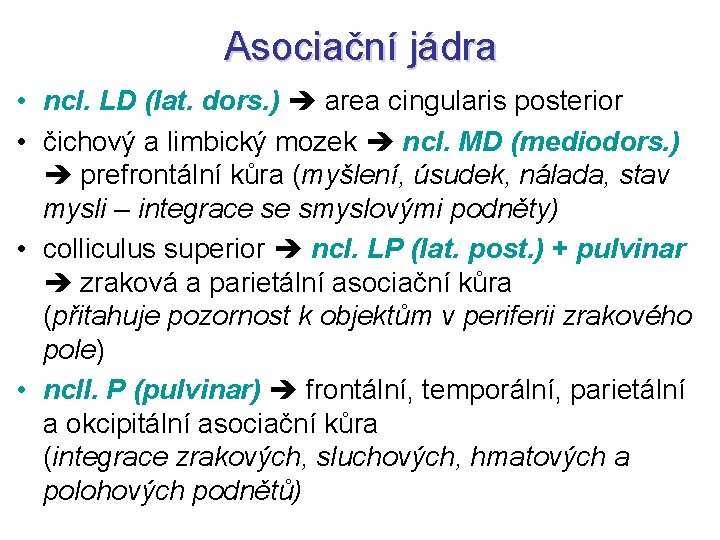

Asociační jádra • ncl. LD (lat. dors. ) area cingularis posterior • čichový a limbický mozek ncl. MD (mediodors. ) prefrontální kůra (myšlení, úsudek, nálada, stav mysli – integrace se smyslovými podněty) • colliculus superior ncl. LP (lat. post. ) + pulvinar zraková a parietální asociační kůra (přitahuje pozornost k objektům v periferii zrakového pole) • ncll. P (pulvinar) frontální, temporální, parietální a okcipitální asociační kůra (integrace zrakových, sluchových, hmatových a polohových podnětů)